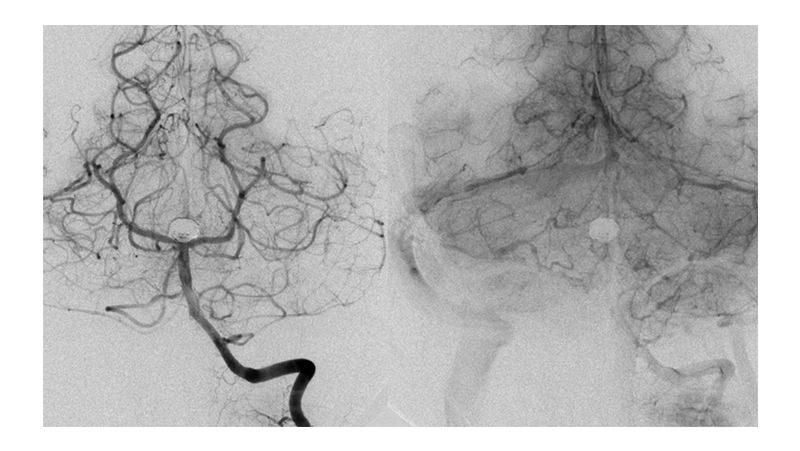

Εικόνα 3: Αγγειογραφία των έσω καρωτίδων αμφοτερόπλευρα, σε πλαγία προβολή: Βλέπουμε την οπισθίων αναστομωτικών ανφοτερόπλευρα. Δεν υπάρχει εφεδρεία από την πρόσθια κυκλοφορία προς το σύστημα των οπισθίων εγκεφαλικών αρτηριών αμφοτερόπλευρα.